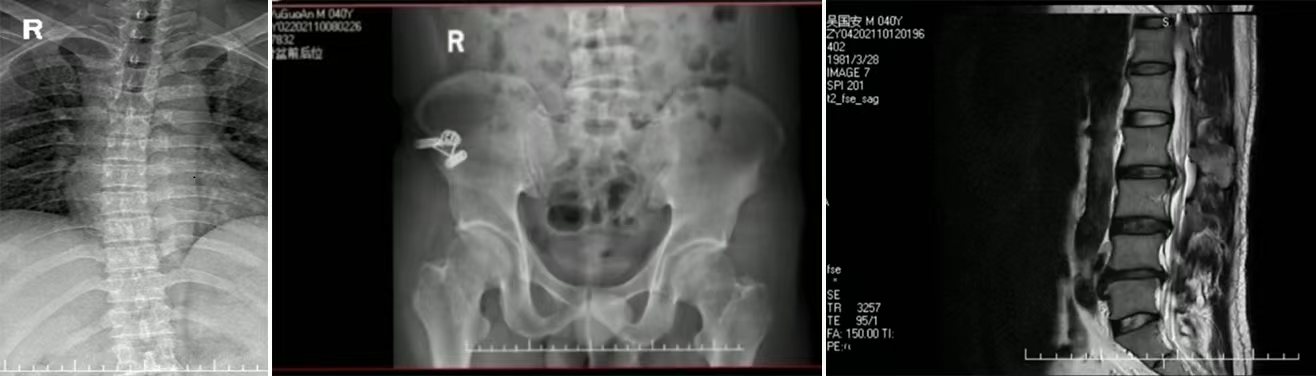

患者吴某安,男,40岁是一名大货车司机,1年前曾因左下肢麻痛,诊断为腰椎间盘突出症,后辗转多家医院治疗,左下肢麻痛反复,一天前因搬重物导致左下肢放射性疼痛加重,无法直立行走,腰椎向左侧凸,拍MR显示左侧1、腰椎退行性变:L2/3椎间盘膨出。L3/4椎间盘膨出并突出(左侧旁中央型),相应左侧椎间孔变窄,椎管狭窄。L4/5椎间盘膨出,相应双侧椎间孔变窄,椎管狭窄,相应水平后纵韧带钙化。查体:左直腿抬高40°,加强试验(+),完善相关检查并常规针灸推拿病情未见明显好转后遂决定进行腰椎穿刺注射合并针刀松解技术。治疗完毕后患者左下肢症状明显改善,三天康复训练治疗后患者脊柱侧弯幅度明显减小,左下肢无麻痛,直腿抬高实验65°加强试验(-),使原本需要手术治疗的患者免挨一刀,收获到患者的赞许。